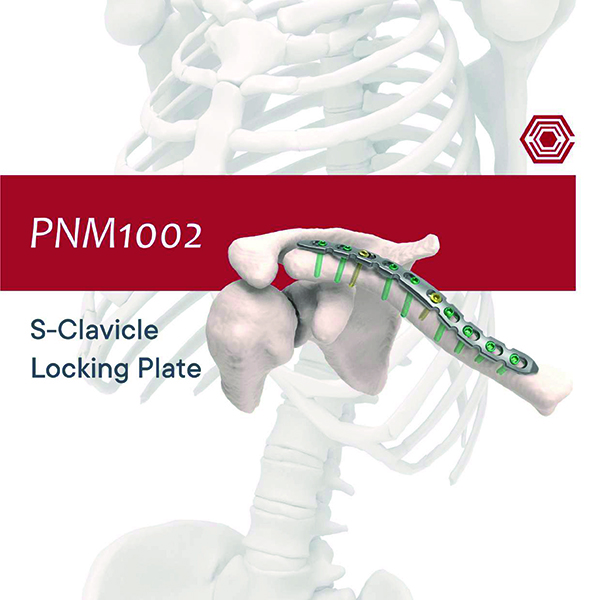

PNM1002 S-Clavicle Locking Plate

Akif Kaya Aybek

Norm Akademi

- Surgical Techniqıe

- Implant Types

- Instrument Container

- Instrument Types